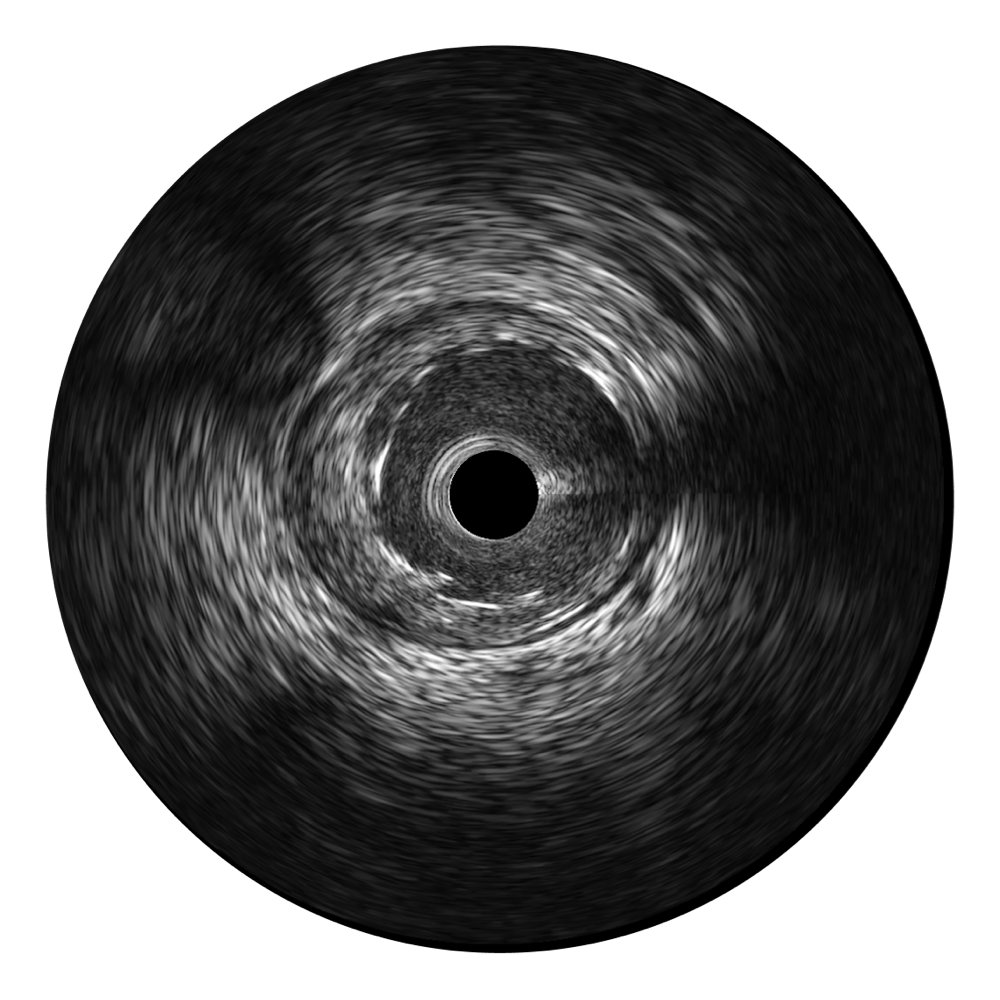

• 玖鼎集团宽频IVUS图像

• 传统IVUS图像

对比传统IVUS导管成像,玖鼎集团宽频IVUS图像的近场支架梁显影更细腻,远场中膜外血管仍清晰可辨,兼顾远中近,兼顾分辨力与穿透深度